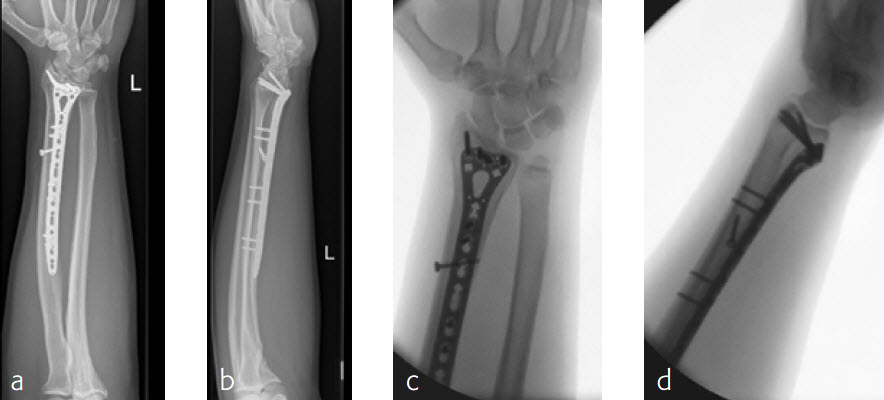

A 26-year-old man suffered a multifragmentary fracture of his left distal radius with extension into the diaphysis (AO23 C3.3) (Fig 1). The VA LCP Extra Long Two-Column plate was used for fixation (Fig 2). After initial immobilization, the plate provided a good postoperative fixation of the fracture.

The fracture showed primary bone healing without callus formation. At the 3-month follow-up, the patient was full weight bearing with excellent clinical function (Fig 3). The radiological follow-up can be technically challenging due to the correct focus of the central ray.